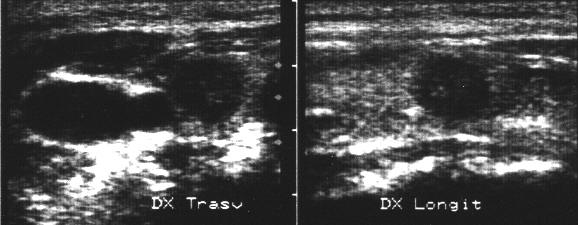

Lob drept in proiectie trasversala si longitudinale.

Lob drept, trasversal si longitudinale.

Lob drept, bazal, trasversal.

Femeie 34 ani. Lesiuni multiple, hipoecogene, difuze,

toti sub un centimetru, in tiroida de dimensiuni normale.

Examen citologic: carcinom papilar.

Examen histologic: carcinom papilar multifocal (4 noduli la dreapta, cu microfocalitati

in stanga ( cel mai mare de 3 mm).